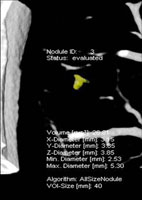

其中,雙射源電腦斷層掃描儀,其輻射量低、檢查速度快,專長於心臟血管檢查及低劑量肺癌篩檢。就心臟冠狀動脈檢查而言,不需任何藥物降低心跳次數,便可獲得清晰且具診斷價值的高解析度影像;低劑量肺癌篩檢,可發現4mm以下的微小病灶。

肺部電腦斷層掃描使用CAD功能所偵測到的影像,經放大後發現其為長3.85mm寬3.15mm的小結節。